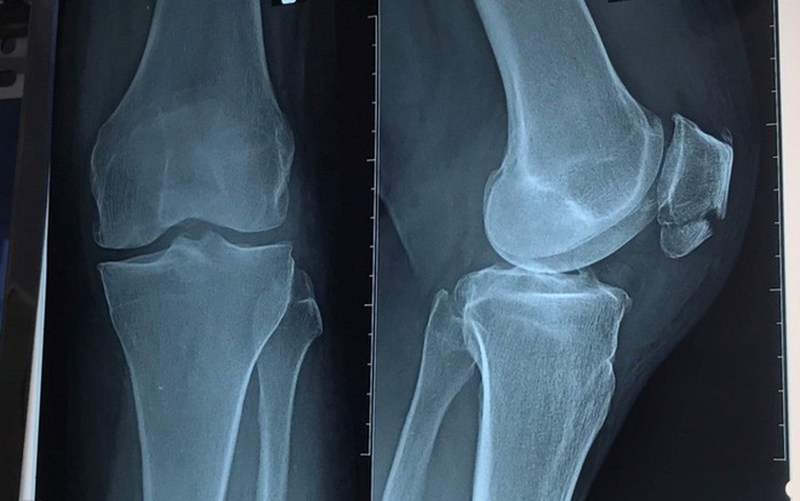

Sau khi thăm khám, chụp X - quang và các xét nghiệm khác, bác sĩ sẽ chỉ định phương pháp điều trị phù hợp:

- Điều trị bảo tồn gãy xương bánh chè không di lệch (2 mảnh và lồi mặt khớp xương bánh chè, lồi cầu đùi không cong) hoặc áp dụng cho bệnh nhân cao tuổi không thể đi lại hoặc gặp các vấn đề nghiêm trọng về sức khỏe.

- Phẫu thuật được chỉ định cho gãy xương , 2 mảnh gãy cách nhau trên 4mm, gãy khi bề mặt khớp của các mảnh gãy bị xoắn lại hoặc có mảnh di chuyển trong khớp gối. Có thể tiến hành mổ khớp để buộc dây thép, mổ buộc xương chữ U, phẫu thuật bằng vít hay mổ với neo chịu lực. Nếu gãy quá nặng, xương bánh chè phải được phẫu thuật cắt bỏ.